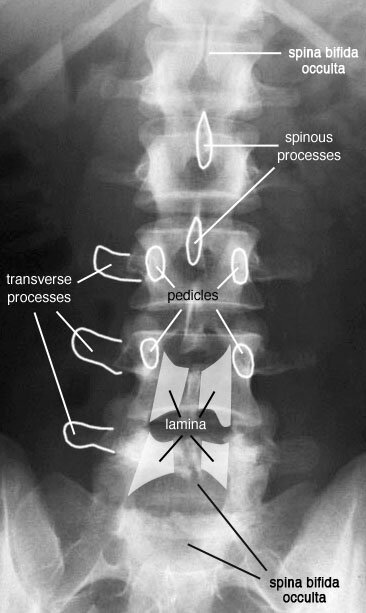

Наш позвоночник представляет из себя четырежды изогнутый столб из позвонков, с "прокладками" из хрящей (межпозвоночных дисков) между ними, соединённых между собой кучей разнообразных связок и укрепленный со всех сторон мышцами.